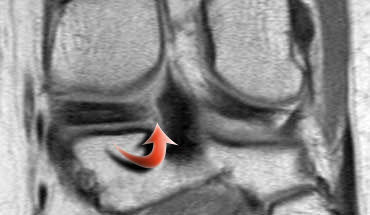

Đây là một trường hợp rách chân sụn chêm trong khác.

Lưu ý rằng sừng sau không còn bám vào xương chày.

Thay vào đó, có thể thấy một khoảng hở (mũi tên cong).

Những tổn thương rách này rất dễ bị bỏ sót khi người đọc nhầm tưởng sừng sau vẫn bình thường.